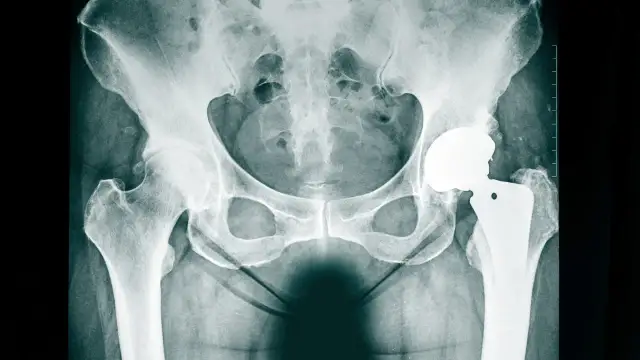

Jak długo odczuwa się ból po endoprotezie biodra? Oczekiwania i fakty

Dowiedz się, jak długo odczuwa się ból po endoprotezie biodra oraz jakie są oczekiwania i metody łagodzenia dyskomfortu po operacji.